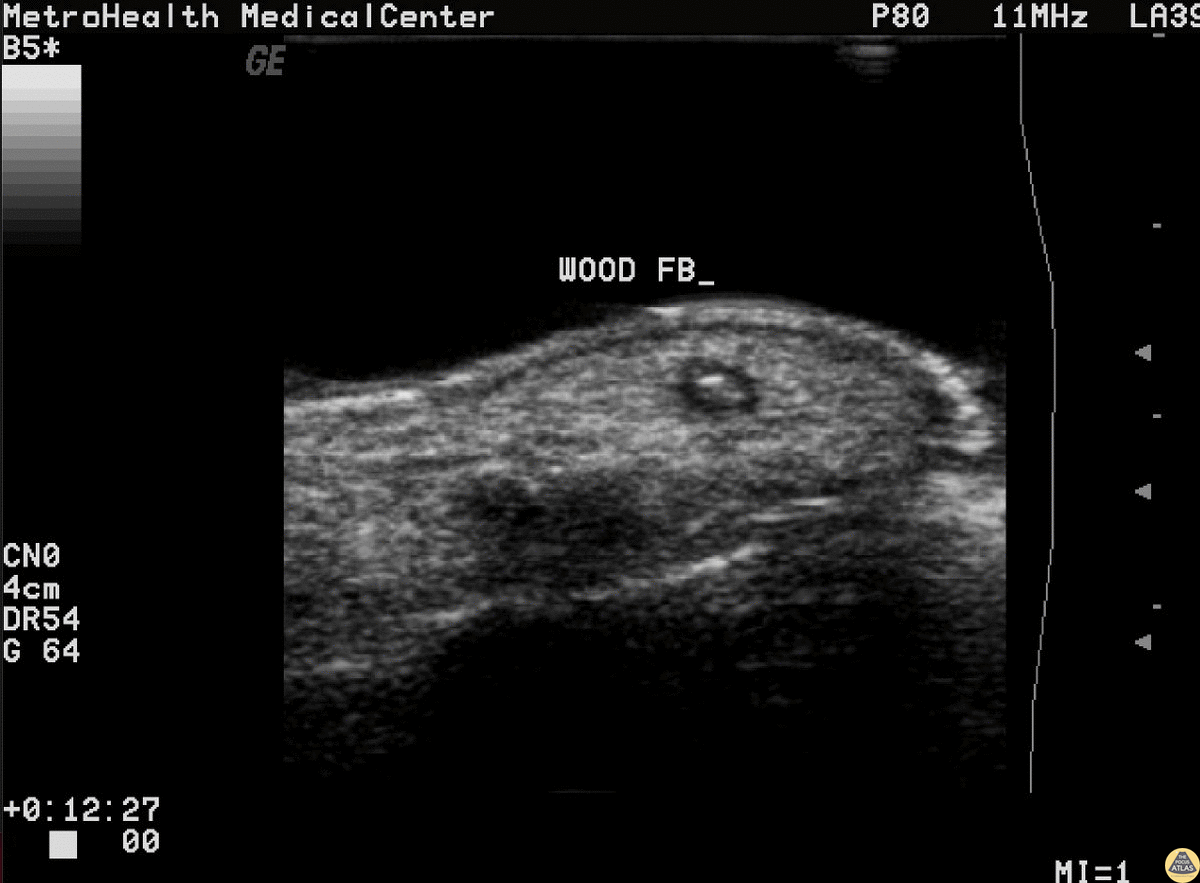

Wooden splinter located in the distal fingertip. Ultrasound shows a halo indicative of edema surrounding the foreign body. Image courtesy of Robert Jones DO, FACEP @RJonesSonoEM Director, Emergency Ultrasound; MetroHealth Medical Center; Professor, Case Western Reserve Medical School, Cleveland, OH View his original post here